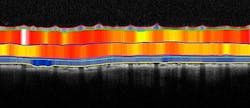

Phoenix Research Labs and Voxeleron (both in Pleasanton, CA) have partnered to lead in the development of optical coherence tomography (OCT) segmentation software. The strategic partnership will enable the two companies to apply Voxeleron's segmentation technology to Phoenix's Image-Guided OCT data, thereby allowing users to readily analyze retinal layers and precisely measure changes to thickness and structure over time.

Voxeleron's algorithms allow automatic analysis of layer thickness in the mouse and rat eye, explains Phoenix Research founder and CEO Bert Massie, Ph.D., while Phoenix's Image-Guided OCT data provides a precise and documented location for the OCT scan. Both will work with the company's InSight XL automated analysis tool to facilitate longitudinal studies, he adds.